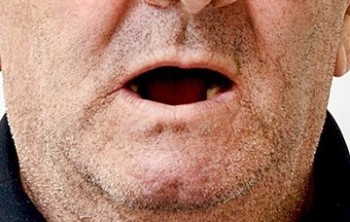

21 работа в портфолио